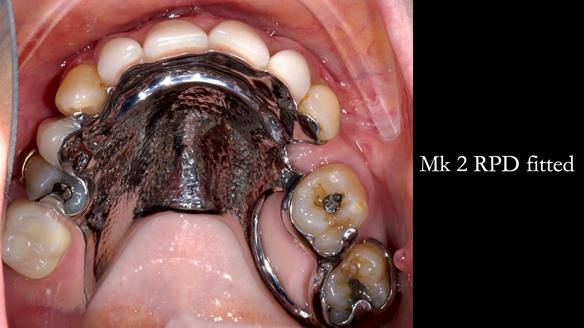

Jean’s Class I Mod III RPD: Learning from My Mistakes – From a Fractured Mk1 to a Stronger Mk2 (4 Years On)

In this edition, I present the removable partial denture treatment for Jean, an 80-year-old woman with a sore mouth caused by a soft tissue-supported 'gum stripper' acrylic denture and a clenching habit. Below, I outline the step-by-step process of her treatment. It wasn't straightforward; I had to remake the denture after it fractured to achieve a satisfactory result. Each patient is unique, and sometimes a new RPD serves as a prototype. Occasionally, I need to make adjustments, learn from any mistakes, and refine the design to get it right.

The treatment has been a success over the past 4 years.